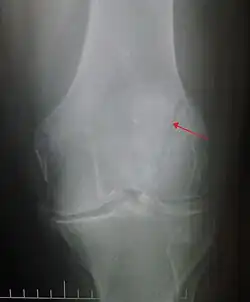

Some people have a normal bipartite patella or two-part patella which can appear as a fracture. The fragment is usually seen in the top outer corner of the patella and can be distinguished from a fracture by being present in both knees.[6]

The patella can break in various ways depending on the way it is injured, and into two or more pieces.[1] Types include transverse, the most common, with one fracture line;[5] marginal; osteochondral; and the rare vertical type, or stellate, where a direct compression force gives rise to a comminuted pattern.[5][7] Patella fractures can be further classified as displaced, where the broken ends of bone do not line up correctly and separate by more than 2mm, or undisplaced and stable where pieces of bone remain in contact with each other.[1][7] If fragments of patella bone stick out from the skin it is known as an open patella fracture, and closed if the overlying skin is intact.[1]

Transverse fracture of patella -

Comminuted fracture of patella -

Osteochondral fracture of patella -

Vertical patella fracture